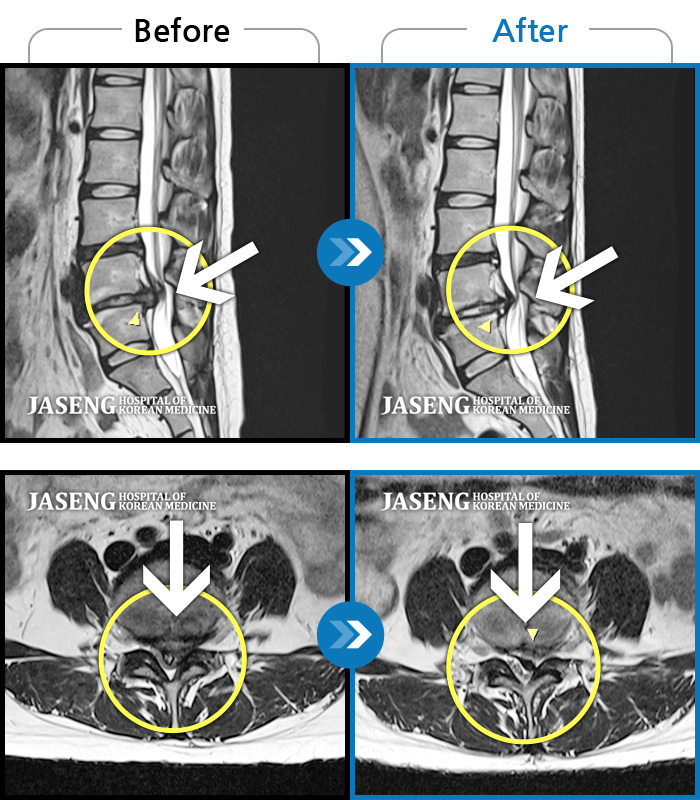

허리디스크

양측 허리 통증, 우측 다리까지 이어지는 통증과 저림, 모든 자세에서 통증 심화

촬영시기

2022.09.02 ~ 2024.08.02

2024.08.14